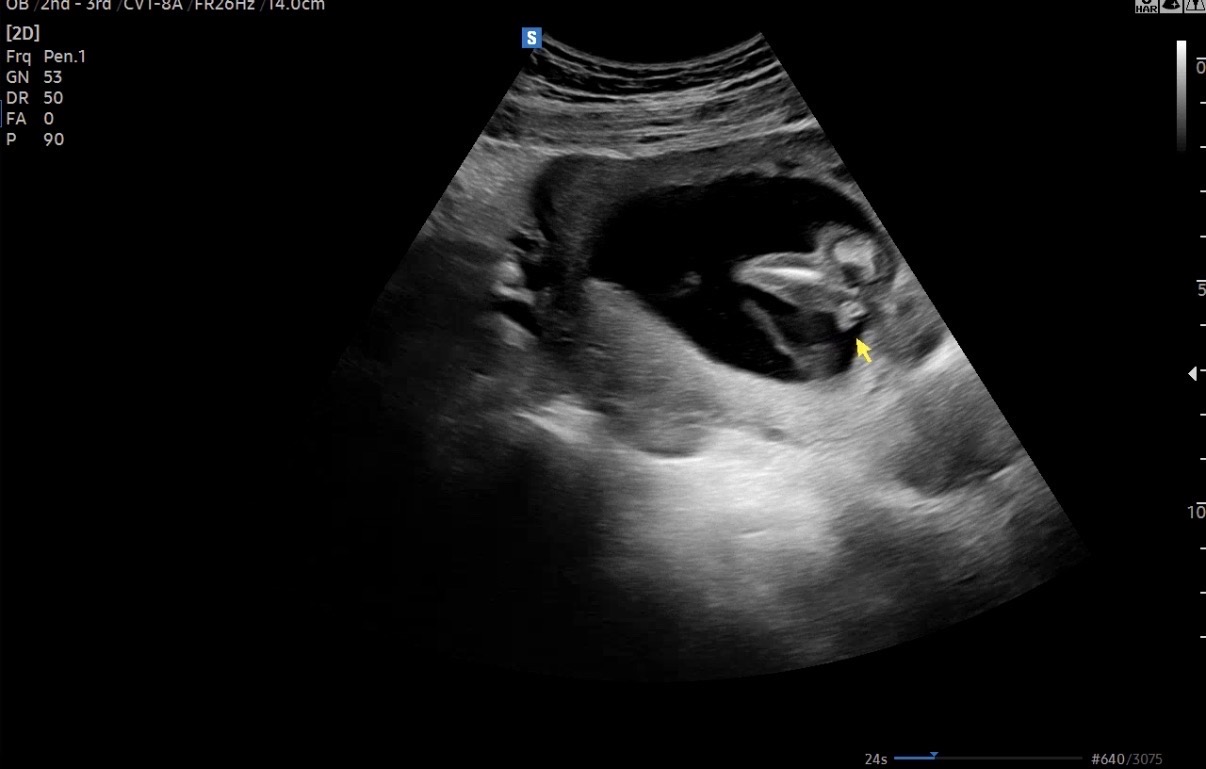

16์ฃผ์ด๊ณ ์ค๋ ๋ณ์๊ฐ์ ๊ฒ์ฌํ๋๋ฐ ์์ฅ๋์ ๋ธ์ด๋ผ๊ณ ํ๋๋ฐ ์ ๊ฐ ๋ณด๊ธฐ์๋ ๋ค๋ฆฌ์ฌ์ด์ ๋ญ๊ฐ ์๋๊ฒ์ฒ๋ผ ๋ณด์ฌ์์ใ ใ ๋ธ๋ง ์๋ค๋ง ์์ธก ๊ฐ๋ฅํ ๊น์ฉ~?